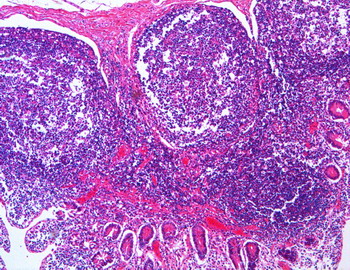

| INM-9

Amígdala palatina (Hematoxilina-eosina) |

Visión general:se aprecia en superficie y en las criptas amigdalares el revestimiento epitelial pluriestratificado pavimentoso no queratinizado característico. A nivel subyacente destaca el tejido linfoide difuso y nodular con predominio de los folículos o nódulos secundarios.

Visión específica:el tejido linfoide difuso, que se encuentra en íntima relación con el epitelio y rodeando los nódulos linfoides, está constituido fundamentalmente por linfocitos de pequeño tamaño y plasmocitos. Los linfocitos están en intima relación con las células epiteliales de las criptas llegando a verse infiltradas por ellos en sus zonas más profundas. Los nódulos linfoides secundarios presentan una cubierta celular densa oscura constituida por los linfocitos de pequeño tamaño que configuran el manto o casquete y un centro claro con población celular heterogénea destacando celulas grandes centroblásticas junto con células de menor tamaño de núcleo hendido de tipo centrocítico de la estirpe linfocitaria.